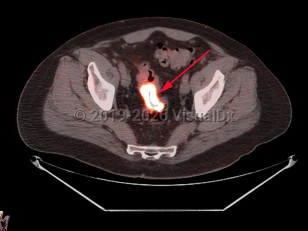

Uterine fibroidsUterine fibroids